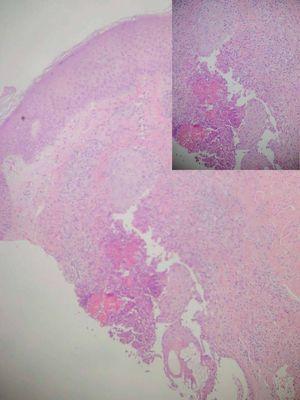

Mujer de 35 años sin ningún antecedente médico-quirúrgico de interés y sin tratamiento farmacológico habitual, que consultó por una dermatitis pruriginosa de 4 meses de evolución, refractaria a diversos tratamientos prescritos (antibióticos y corticoides orales, así como dapsona). La erupción se inició en glúteos y posteriormente se fue extendiendo a cara, tronco y extremidades. La exploración cutánea reveló la presencia de múltiples pápulas y pústulas foliculares, que llegaban a formar placas en alguna zona y se apreciaba en otras un crecimiento excéntrico, adoptando una morfología anular. Afectaba principalmente la cara, cuello y tronco, pero también las extremidades superiores e inferiores, incluyendo además ambas palmas de las manos (figs. 1 y 2). No presentaba adenopatías, ni se palpaban organomegalias. El cuadro clínico evolucionaba de forma progresiva, con aparición de nuevas lesiones, persistiendo muchas de ellas, e involucionando otras dejando hiperpigmentación residual. Se habían realizado 2 biopsias en otro centro con diagnóstico histológico de dermatosis pustular subcórnea. En nuestro Servicio se efectuaron nuevas biopsias y en todas ellas se apreciaban hallazgos semejantes, con pústulas subcorneales sin ninguna relación con folículos, acompañadas por un denso infiltrado eosinofílico. Continuaron realizándose estudios histológicos hasta demostrar la presencia de un infiltrado de leucocitos polimorfonucleares con elevada proporción de eosinófilos a nivel del infundíbulo, llegando a destruirlo en alguna zona (fig. 3). Este infiltrado también se observaba focalmente en las glándulas sebáceas y producía en alguna ocasión espongiosis, pústulas y/o abscesos foliculares eosinofílicos.

Fig. 3.--Se observa destrucción de pared de folículo piloso por un infiltrado inflamatorio, con abundante material granular eosinofílico procedente de eosinófilos degranulados (figuras en llama). Ver aproximación.